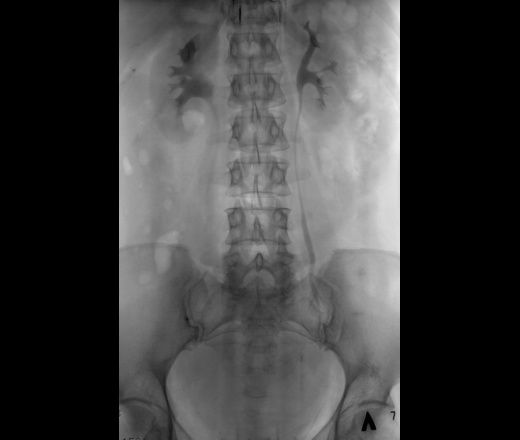

Классика жанра. Внутривенная урография.

Обзорный не делали.

камень правого мочеточника, осложненный гидронефрозом?

R- негативный

Фрагменты рентгенограмм.

Неполная стриктура пиелоуретерального сегмента с престенотическим расширением лоханки с наличием "псоас-симптома".

Раз классика жанра, значит должно быть что-то известное. Но просто узнаваемого не вижу. Имеется субкомпенсированная стриктура лоханочно-мочеточникового сегмента правой почки с развитием гидрокаликоза и пиелоэктазии (гидронефрозом не назову, т.к. паренхима не истончена), да, с "+" псоас симптомом. Однако, постстенотическое расширение правого мочеточника, плавно теряющее контраст дистально, обусловлено гигантской миомой матки, сдавливающей мочеточник извне. Странно, как слева того же не произошло.